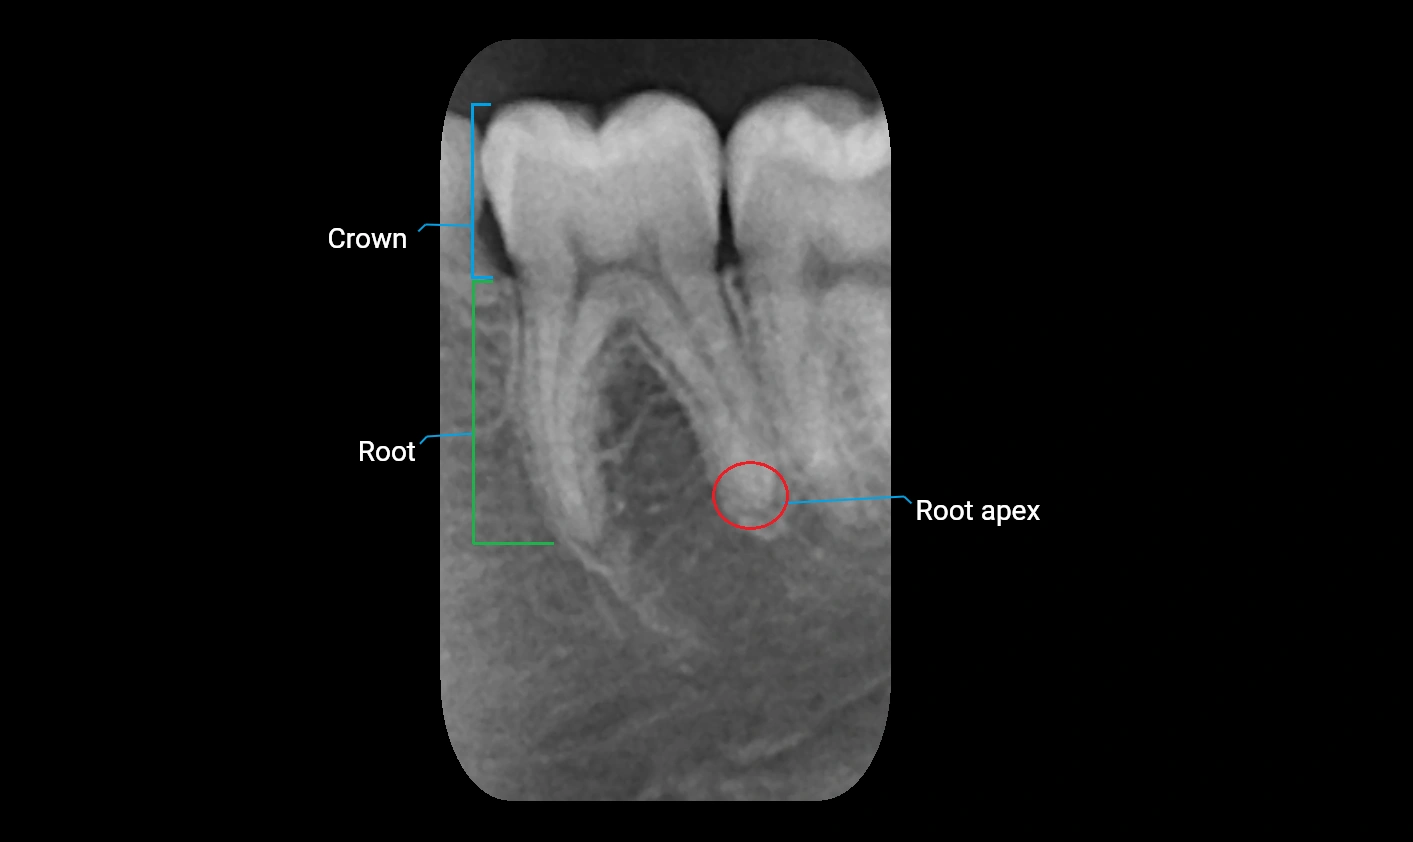

STIR (Short Tau Inversion Recovery):

• Suppresses fat signal to highlight edema, infection, or bone lesions

• Normal alveolar process shows low cortical signal with intermediate trabecular signal

• Pathological changes, including osteomyelitis, cysts, or tumors, appear bright hyperintense